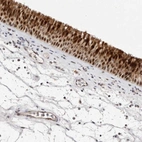

Immunohistochemical staining of human nasopharynx shows strong cytoplasmic and nuclear positivity in respiratory epithelial cells.